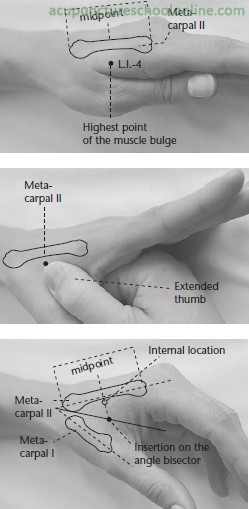

On the dorsum of the hand, between the first and second metacarpal bones, at the modpoint of the second metacarpal bone and close to its radial border

Perpendicular insertion 0.5 - 1 cun

Oblique insertion directed proximally 1 - 1.5 cun

Basic information on location, needle depth, TCM actions, indications and combinations is taken from Deadman et al (2001): A Manual of Acupuncture with additional anatomical information researched by reference to Gray's Anatomy (38th Ed., 1995) unless otherwise referenced. Images were found on acupunctureschoolonline.com and can be traced back to Claudia Focks (2008) Atlas of Acupuncture originally. I cannot claim any credit or rights over them. Other sources should be quoted in the text.